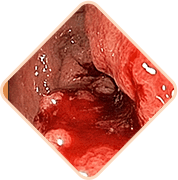

Krvarenje tijekom stolice ili vježbanja

Ispunjene žile hemoroidne kvržice vrlo su slabe. Često puknu. Stupanj gubitka krvi u ovom slučaju može biti takav da je potrebna transfuzija krvi